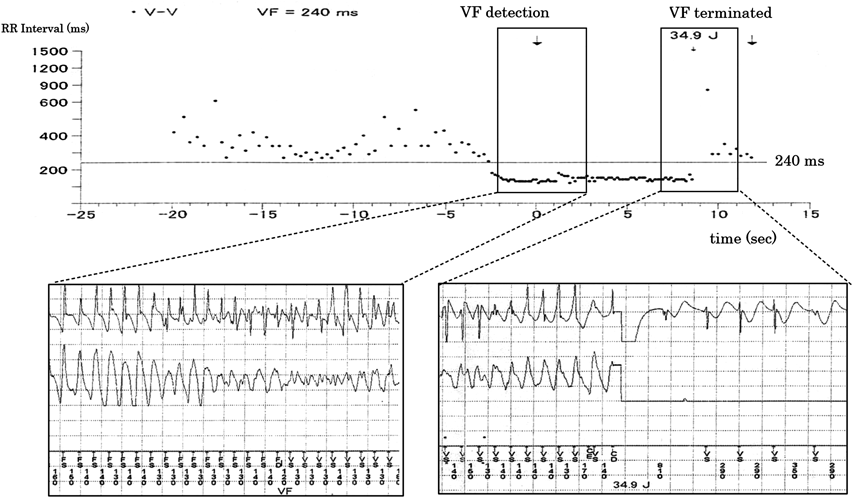

複数の突然死を有するカテコラミン誘発多形性心室頻拍の一家系A Large Family Report of Catecholaminergic Polymorphic Ventricular Tachycardia with Sudden Cardiac Death